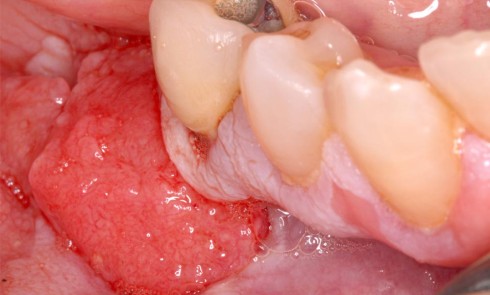

Contexte – Processus de décision La traction des lambeaux, nécessaire pour assurer la fermeture primaire des berges lors des procédures...